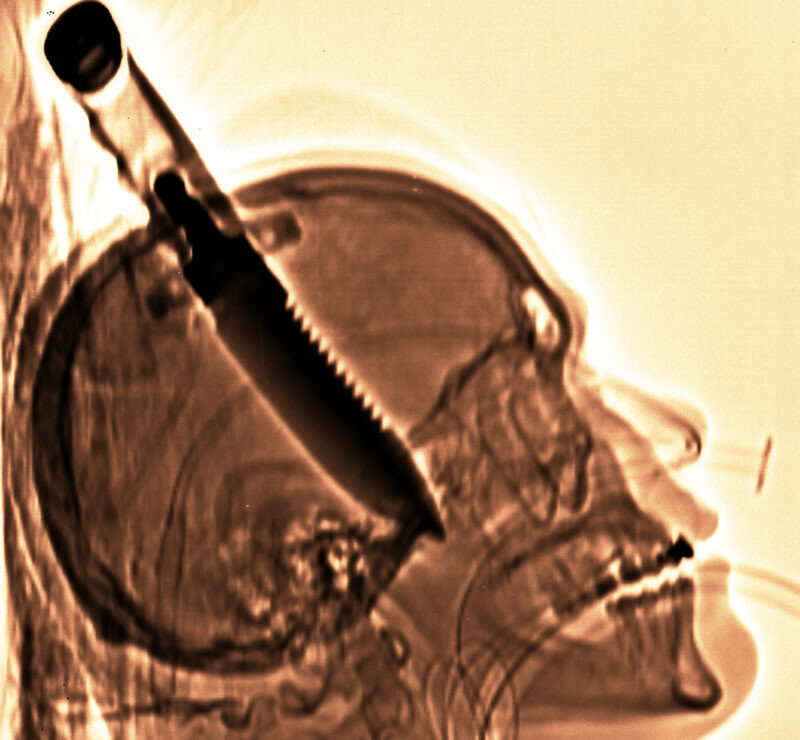

Нож в голове. Записки травматолога.

Посреди коридора стоит бабушка - божий одуванчик, а прямо из головы в районе темени у неё торчит здоровенный нож. То, что он здоровенный, мне как-то сразу становится очевидно. Т.к. и рукоятка не маленькая и часть клинка видна.

Навскидку с мозговой симптоматикой всё нормально. Ну есть лёгкий нистагм, но такой может и без травмы быть. А вот что там с сосудами? Дело ясное, что дело тёмное.

Можно открыть кровотечение, если пошевелить железяку в черепе.

А если кто думает, что это враки всё, то это просто по незнанию. Люди с такими травмами головы выживают иногда, что просто диву даёшься.

Тут основное, чтобы не были повреждены стволовые структуры, отвечающие за витальные функции. Всякие там сосудодвигательные и дыхательные центры, и т.п.

А так-то мозг к боли не чувствителен вообще. Чувствительны ткани мозг окружающие: кожа, надкостница, оболочки мозга... Так что если сам мозг что-то и проткнёт, то это пострадавший не почувствует. Вот от окружающих тканей боль будет. Ну так мало ли как люди повреждаются. И ничего. Больно, но терпимо.

Ну и второе, чтобы сосуды не сильно повредились, чтобы кровоизлияние не стало причиной смерти.